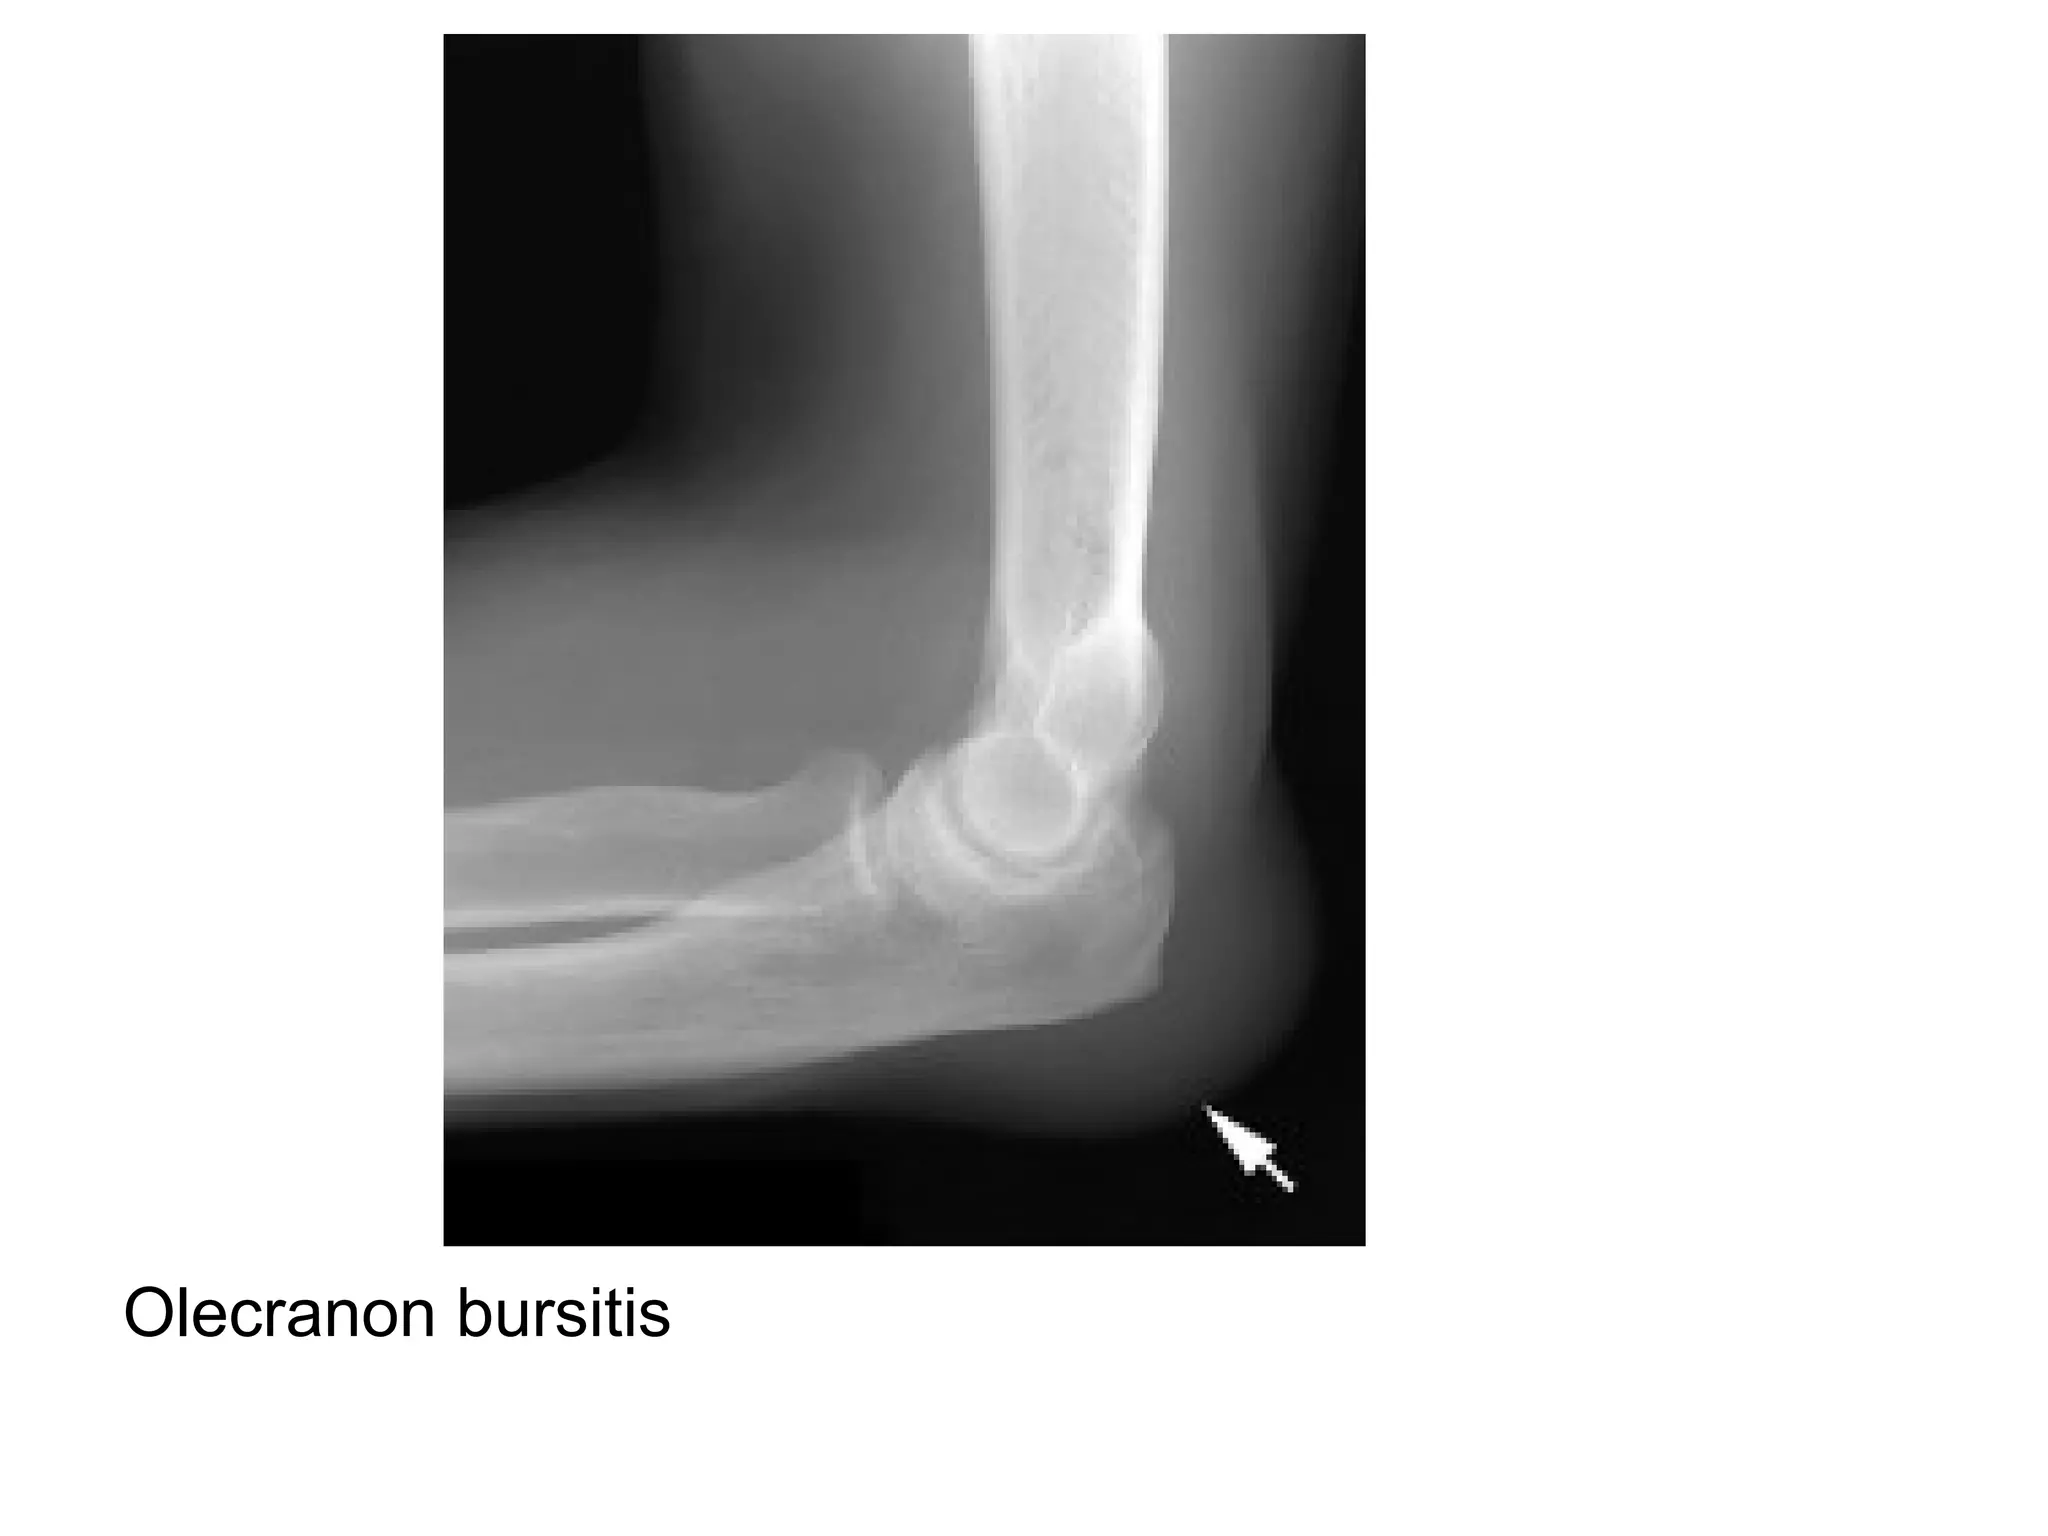

Olecranon bursitis

Gout-Olecranon Bursitis , there is soft tissue swelling in the olecranon

bursa (white arrow) , a finding suggestive of gout , there are also

erosions (blue arrows) around the elbow joint